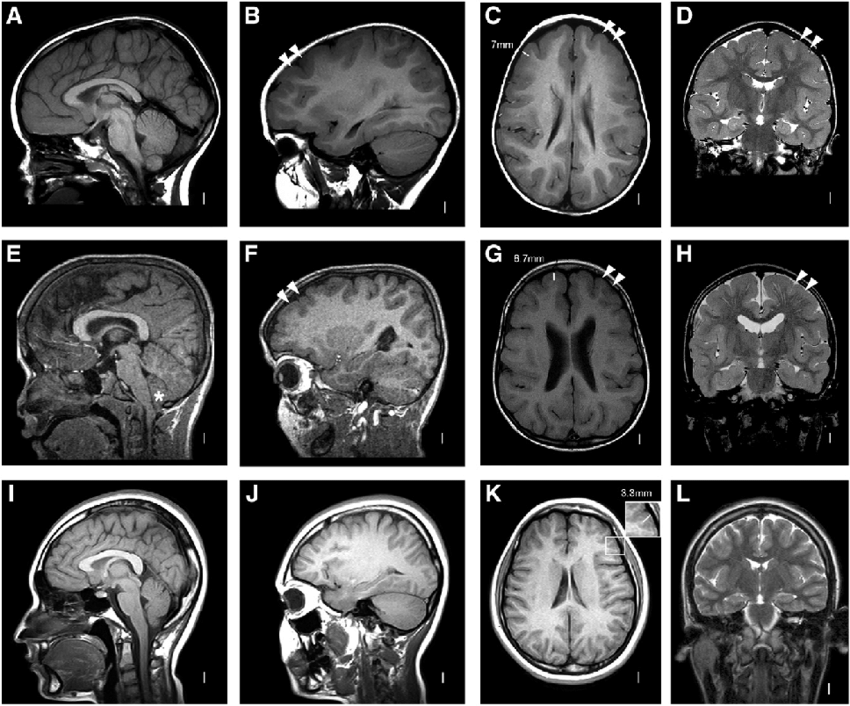

Диагностика липомы головного мозга на МРТ

Формирование липомы всегда проходит бессимптомно, и увидеть ее можно только при аппаратной диагностике на МРТ головного мозга или КТ. В ходе сканирования на снимках врачи отметят жировое образование, оценят его размеры и местоположение и решат, насколько эта опухоль изменяет соседние ткани. По данным томографии головы врачи могут принять решение о целесообразности хирургического удаления жирового образования.

Липома головного мозга на МРТ достаточно четко визуализируется на любимой модели томографа. Диагностировать ее можно при МРТ головного мозга даже без применения контраста, поскольку МР сигнал от жирового образования очень специфичный, дифференцировать липому от других видов опухолей тоже не составит труда.

По итогам томографии пациент получит заключение врача, записанное на дисковый носитель, и рекомендации по следующим шагам. С этим рентгенологическим заключение следует прийти на прием к своему лечащему врачу и вместе с ним выработать план действий. Если на МРТ обнаружили маленькую липому, скорее всего врач предложит проводить наблюдение. Для этого раз в 6 месяцев необходимо будет делать контрольную томографию мозга и сравнивать размеры образования. Если жировая опухоль внушительных размеров, скорее всего доктор порекомендует ее удаление.